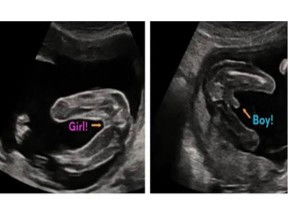

kak klau ini di gambar kok aku gak lihat 2 pangkal paha yaa .. biasanya klau mau lihat jenis klamin d usg ddi bagian 2 pngkal paha kak ..nnti klihatan tuh mana yg ada tonjolan atau gak.. kyak gini kak cntohnya